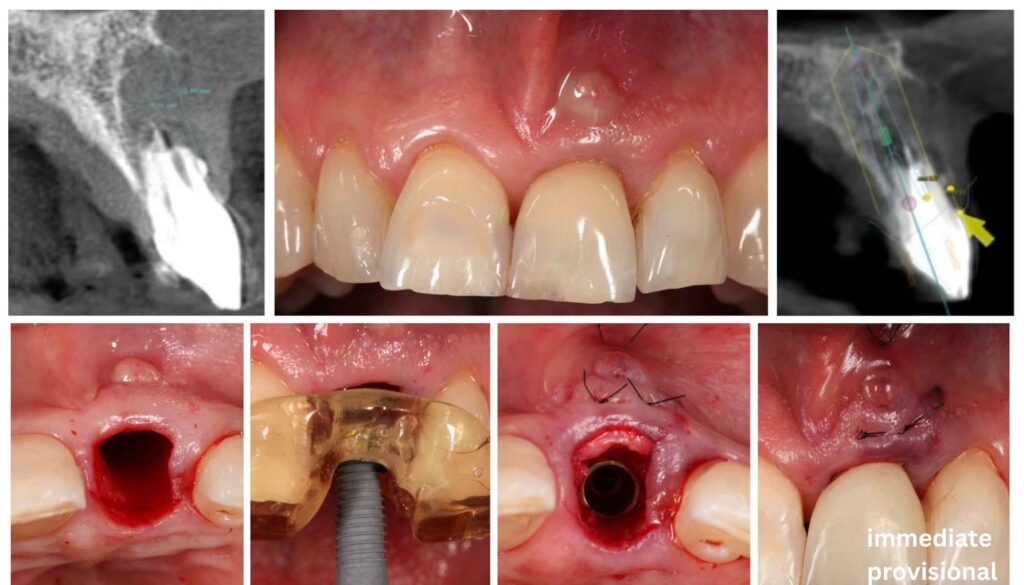

1. Pre-Surgical Assessment and Digital Planning

CBCT evaluation guides implant diameter selection — a paradigm shift from conventional thinking, as IDR uses the fresh socket anatomy differently than traditional protocols. Digital workflow integration allows virtual implant positioning, smile design preview, and fabrication of a provisional prosthesis before the surgery begins.

2. Atraumatic Extraction with Tissue Preservation

Periotomes, thin-bladed luxators, and rotational forces minimize trauma to the alveolar housing. The periosteum is left intact. No flap is raised. This flapless approach preserves the blood supply to the crestal bone — a critical factor in maintaining the buccal plate that is so often sacrificed in conventional extractions.

3. Socket Debridement and Implant Placement

After thorough curettage of granulation tissue and any infected material, the implant is placed with precise three-dimensional positioning. Tapered, deep-threaded implants with moderately to highly roughened surfaces are preferred to maximize primary stability in the incompletely healed socket environment.

4. Maxillary Tuberosity Harvest

Under local anesthesia, a minimally invasive approach exposes the tuberosity. Cortico-cancellous block, particulate cancellous bone, and connective tissue are harvested as the Triple Graft. The harvest site heals uneventfully and patients typically report minimal discomfort beyond the implant site itself.

5. Flapless Bone Reconstruction

The autogenous graft is packed into the gap between implant and socket walls, filling bony deficiencies and establishing a biological seal. Unlike membrane-covered grafting approaches that require a second surgery for membrane removal, the flapless IDR approach leaves the periosteum undisturbed, maintaining vascular continuity and greatly simplifying the post-operative course.

6. Emergence Profile Design and Provisional Restoration

A screw-retained provisional crown is placed at the time of surgery, restoring esthetics immediately and shaping the soft tissue emergence profile from day one. The provisional must be out of occlusal contact during the healing phase, but its presence guides the peri-implant gingival architecture toward the desired final form.